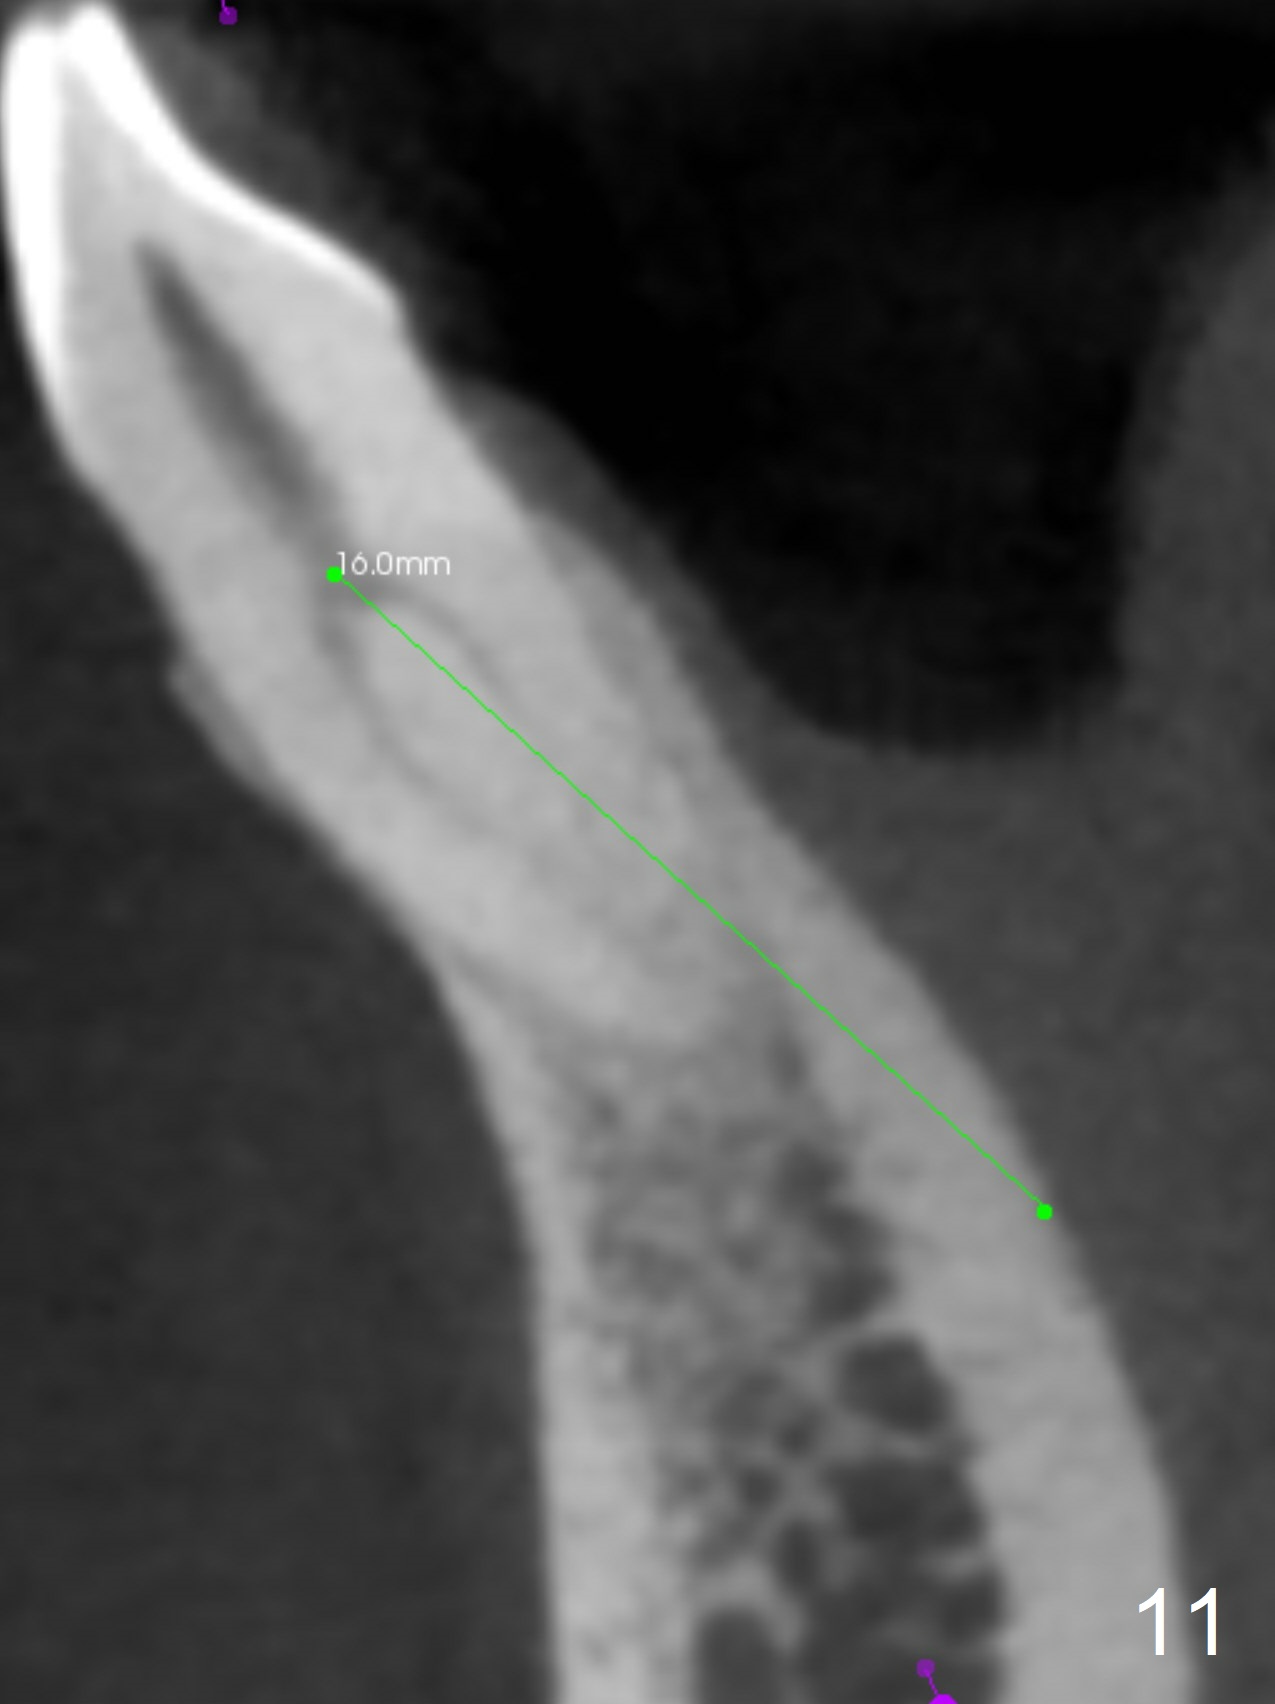

In fact the apex of the lateral incisor is also in the center of the alveolus (Fig.9 *). Osteotomy established in the lingual slope for a long distance (Fig.10,11) will perforate the lingual plate. The correct method of osteotomy is to set up in the middle of the socket and along the long axis of the alveolus with 2 fingers holding the alveolus (Fig.12 (2 circles)). The problem for this case is to use the lower RPD as a guide. With the RPD in place, the tactile sensation is lost.